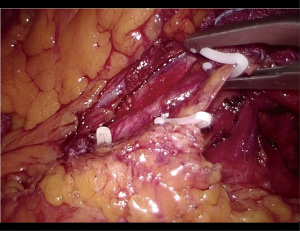

The patient was positioned supine on the operative table with the legs abducted. Under general anesthesia, a cystoscopy was performed, and a 6 Fr Pollack catheter was introduced in the left ureter to allow intraoperative injection of ICG. Pneumoperitoneum was induced through a Veress needle placed in the umbilicus. Four ports (two 12-mm and two 5-mm) were placed as for laparoscopic left colectomy (Figure 6). Upon exploration of the abdominal cavity, the sigmoid was tenaciously adherent to the posterior-lateral aspect of the bladder (Figure 7). The small bowel was retracted away from the operative field. Partial mobilization of the descending and sigmoid colon was performed using the monopolar hook and harmonic scalpel. The inferior mesenteric artery and vein were clipped with Hem-o-lok and sectioned (Figure 8). The left ureter was visually identified and followed along its route toward the pelvis, then it could not be clearly distinguished from the pseudotumor involving the sigmoid colon and the bladder. Infusion of 5 mL of ICG through the ureteral catheter allowed to visualize the left ureter (Figure 9) and guided the dissection of the sigmoid from the bladder wall. At the end of dissection, the bladder wall appeared undamaged, and a methylene blue test was performed to exclude urinary leakage (Figure 10). A 5-cm laparotomy in the right iliac fossa was performed and the Alexis® wound retractor was placed. A curved linear stapler (Contour®) was introduced and sealed with a surgical glove to maintain the pneumoperitoneum. After rectal stapling, a 5 mL intravenous bolus of ICG was injected to test for colonic perfusion and to identify the ideal site for the anastomosis on the descending colon. A standard transanal Knight-Griffen colorectal anastomosis was performed using a 29-mm circular stapler. Two abdominal drains were left in the pelvis, and the abdominal incisions were closed. Total duration of the procedure was 220 minutes, and blood loss was <100 mL. Video 1 shows the whole surgical procedure.